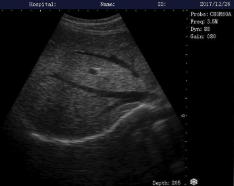

Como hemos indicado, la ecografía musculoesquelética nos permite visualizar en tiempo real los tejidos blandos como músculos, tendones, ligamentos y nervios. Su uso mejora la precisión en la valoración, el seguimiento de lesiones y la aplicación de las técnicas mencionadas arriba. Es una herramienta segura y clave para personalizar los tratamientos y optimizar resultados.